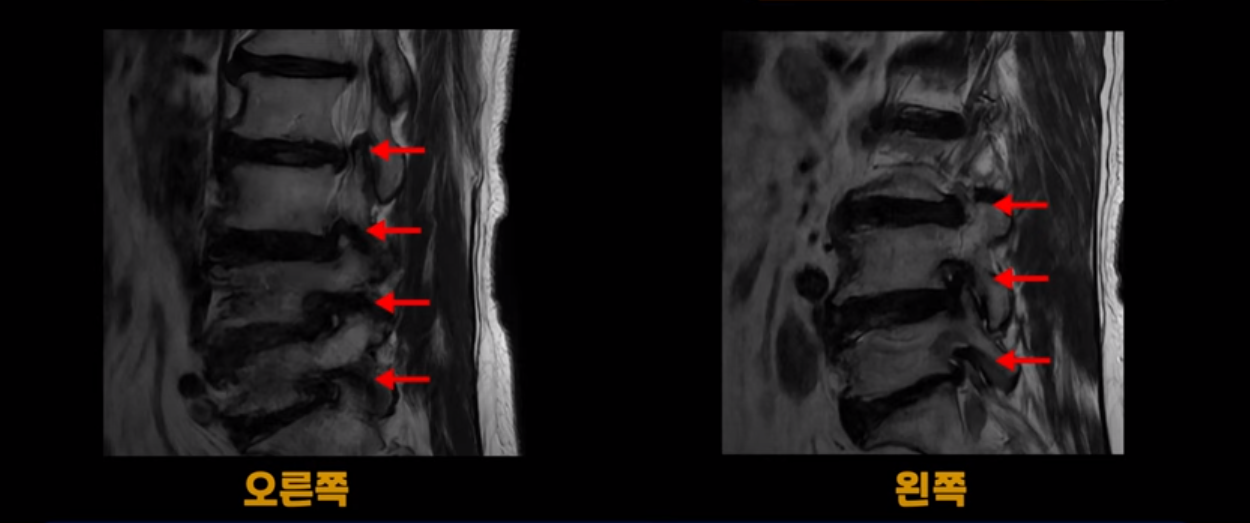

이 환자분은 MRI로 보면 허리 여러 마디가 신경이 매우 심하게 눌려 보이는 분입니다. 이분 MRI를 보면서 간단히 설명해 드린 후 어떻게 이렇게 신경이 심하게 눌린 환자분이 수술 없이 근육신경재활치료로 좋아질 수 있는지, 다리가 아파 걷지 못하는 환자가 어떻게 안 아프고 잘 걸을 수 있게 되는지, 10년 동안 괴로웠던 양 발의 시린 증상은 어떻게 사라질 수 있는지, 치료는 어떻게 하는지 자세히 설명 드리겠습니다.

MRI 보시면 (2-8) 허리의 5마디가 전부 다 심하게 퇴행되어 있습니다.

5마디 전부 다 심한 중심성 협착이 있습니다.

1번 2번,

2번 3번,

3번 4번,

4번 5번,

5번 6번

이렇게 모두 다 심하게 막히는 경우는 드문데요. 또한 오른쪽, 왼쪽 신경이 빠져나가는 추간공도 다 심하게 막혀있습니다.

오른쪽, 왼쪽 이렇게 신경 구멍들이 다 좁아지고 신경이 눌리니까 양쪽 다리가 발바닥까지 아파서 걷기 어렵고 양쪽 발이 10년 넘게 시린 겁니다. 당연히 수술해서 눌린 신경을 풀어줘야 한다고 들으셨는데요. 이런 환자분을 어떻게 수술 없이 치료할까요? 지금부터 설명해 드립니다.